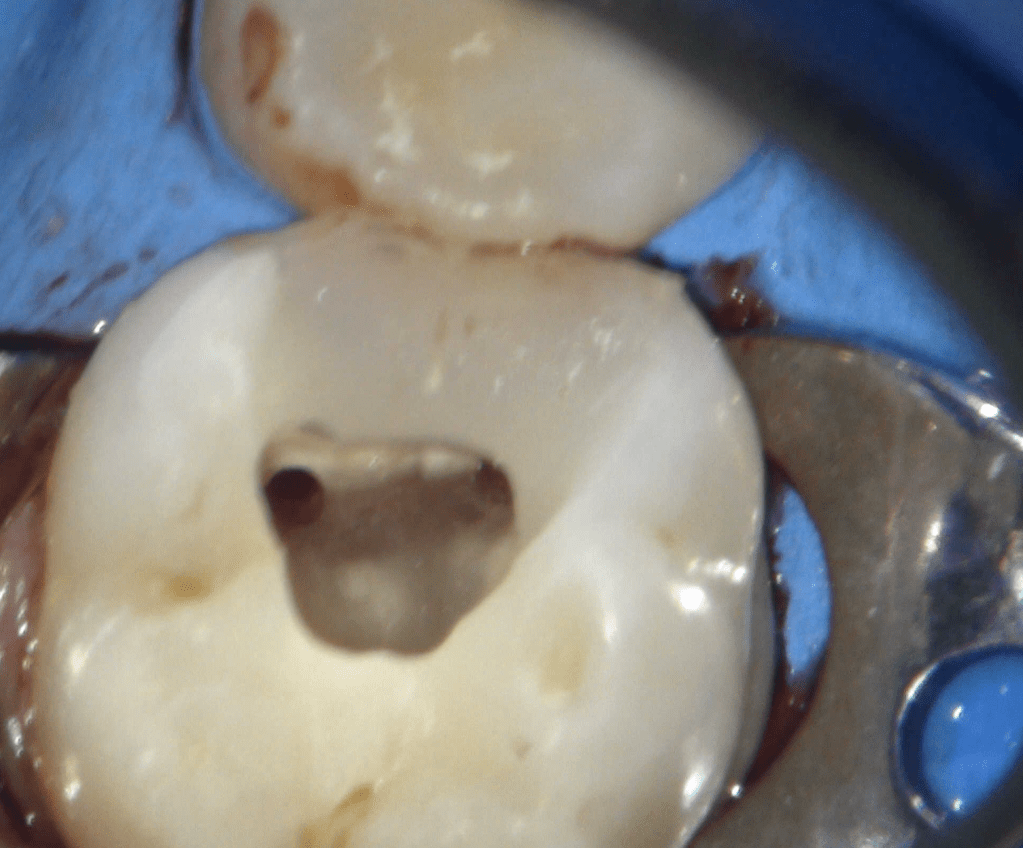

Reco pre-endo, molar inferior